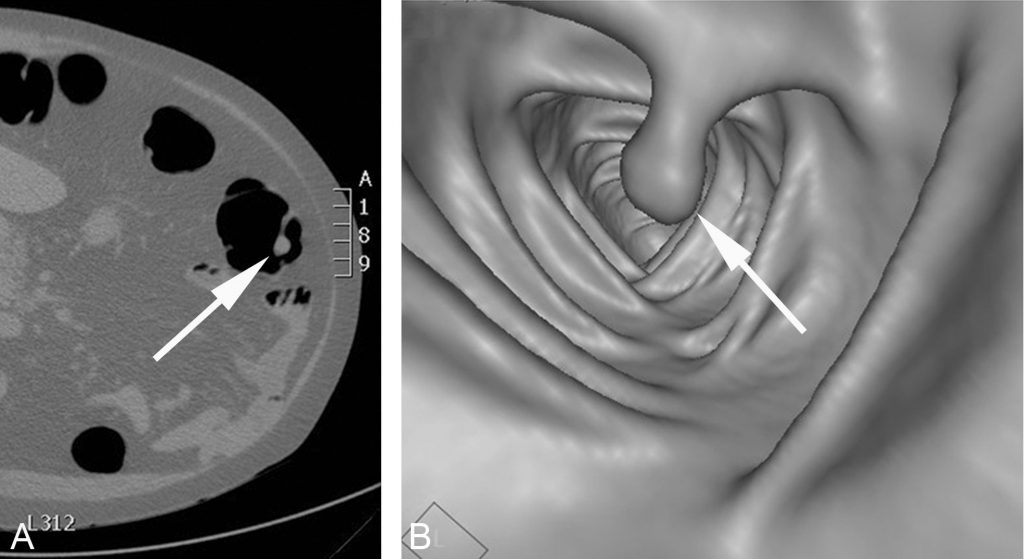

En France, le dépistage systématique du cancer du côlon consiste en la réalisation tous les 2 ans de 50 à 74 ans d’un test immunologique à la recherche de sang dans les selles, suivi d’une coloscopie optique en cas de résultat positif. Une technique particulière de scanner abdominopelvien, appelée coloscopie virtuelle, effectuée après préparation du côlon pour éliminer les matières fécales, distension par gonflage au CO2 et reconstruction 3D de la lumière, permet également de mettre en évidence les petites tumeurs et les polypes précancéreux sur la muqueuse du cadre colique (figure 15.4). Cette technique ne permet cependant pas la réalisation de biopsie, mais elle peut être employée lorsqu’un patient présente des contre-indications à la coloscopie optique ou lorsque celle-ci est incomplète.

Fig. 15.4. Exemple de coloscopie virtuelle au scanner.

L’acquisition axiale après distension du côlon par insufflation de CO2 par l’anus montre un petit polype pédiculé (flèche) dans la lumière du côlon descendant (A). Ce polype est mieux visible sur la reconstruction 3D endoluminale du côlon imitant une image endoscopique (B).

Source : CERF, CNEBMN, 2022.